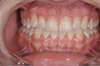

AVANT

Réalisation d'une facette céramique sur l'incisive droite qui présentait un composite disgracieux. La dent est légèrement préparée. Une dent provisoire est mise en place entre les deux séances. Un collage est enfin réalisée après validation esthétique.